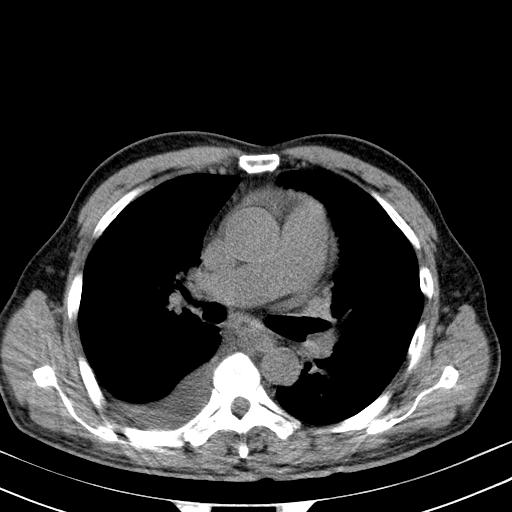

以下是引用zjzjr在2010-3-21 17:39:00的发言:[br]右下中心型肺癌并阻塞性肺炎/不张,纵膈淋巴结肿大,右侧大量胸腔积液,左侧少量胸腔积液

以下是引用zxl51642在2010-3-21 17:06:00的发言:[br]右下中心型肺癌并阻塞性肺炎/不张,纵膈淋巴结肿大,右侧大量胸腔积液,左侧少量胸腔积液,少量腹水。建议纤维支气管镜进一步检查。